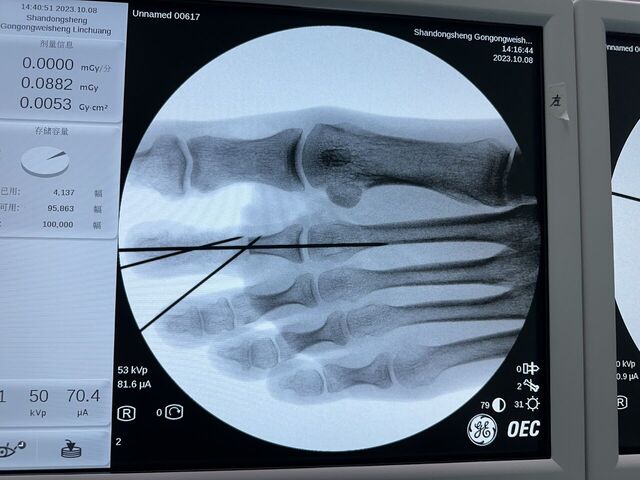

昨天的手术。